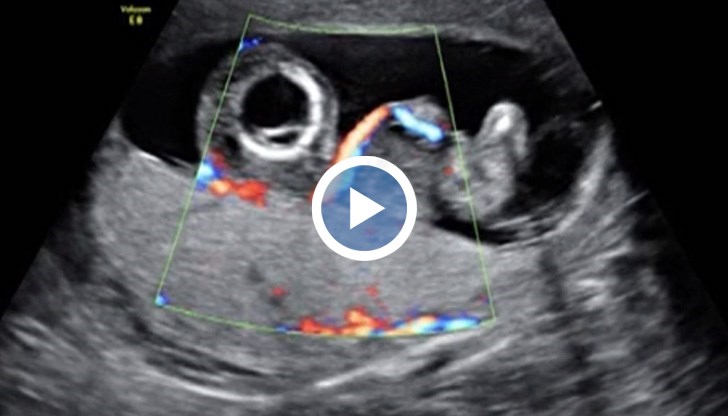

В утробата на майка си то споделя обща плацента със своя еднояйчен близнак без сърце – т. нар. „паразитен близнак”.

Тъй като единият близнак няма развити сърдечни структури, другият го кръвоснабдява и по този начин с напредване на бременността и наедряване на паразитния близнак здравото бебе е изложено на сериозна заплаха да развие сърдечна недостатъчност.

За да се спаси здравото бебе, е предприета вътреутробна операция в 15-ата седмица от бременността. След успешната вътреутробна операция бременността е проследена от екипа на д-р Чачева и благодарение на общите им усилия бебето се ражда здраво и доносено в 38-а гестационна седмица.